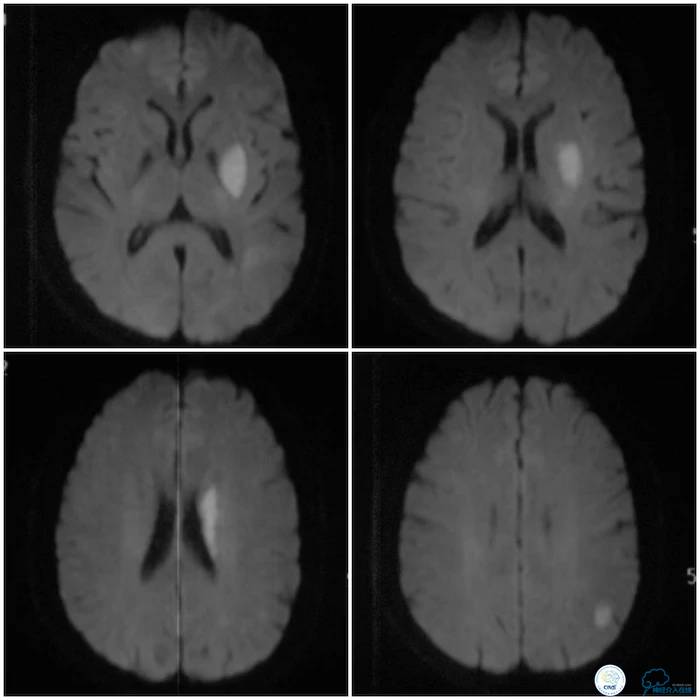

予“拜阿司匹林、氯吡格雷、阿托伐他汀”,治疗症状好转出院。2周前患者症状反复,再次到当地医院就诊,复查头颅MRI示左侧基底节区、放射冠、半卵圆中心、顶叶多发急性脑梗死(图3)。

图3

MRA示左侧大脑中动脉狭窄(图4)。

图4